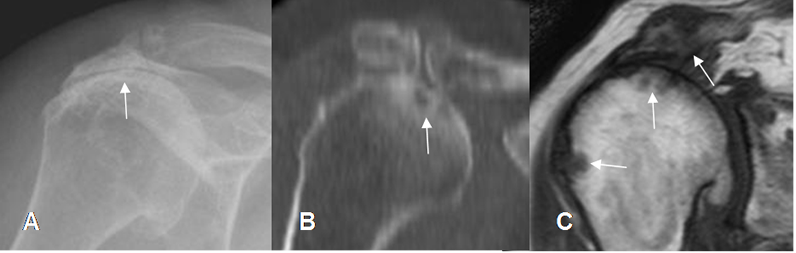

Fig 100. Ruptura del supraespinoso.

A: Rx AP. Cambios degenerativos con pérdida del espacio acromiohumeral y esclerosis asociada, por ruptura del supraespinoso.

B: TAC reconstrucción sagital y C: RM coronal en T1. Ruptura del supraespinoso, con pérdida del espacio acromiohumeral y lesiones osteocondrales.